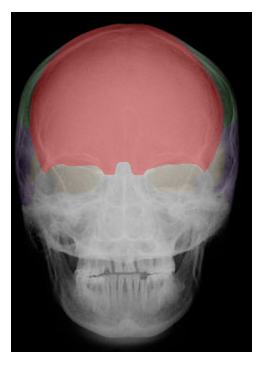

Cranial and Facial Bones

Students will use images and descriptions to reinforce their knowledge of the cranial and facial bones.

| FRONTAL |

in blue,  | OCCIPITAL |

protect the brain | SKULL BONES |

total number of cranial/skull bones | 8 |

in green,  | PARIETAL |